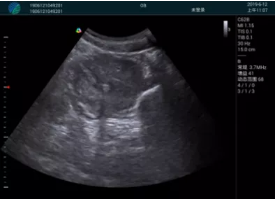

病例一:

清晰顯示孕囊,通過軟件包計(jì)算孕齡7w+6d

M20實(shí)時引導(dǎo),術(shù)中清晰顯示孕囊被破壞和抽吸針的過程,清晰顯示吸引針

抽吸結(jié)束后縱切子宮,孕囊已被完全抽吸,未見明顯殘留

橫切子宮,發(fā)現(xiàn)右側(cè)宮腔靠近宮角處有少許脫模樣殘留

M20引導(dǎo)下,抽吸針找到右側(cè)宮角處再次清掃

二次抽吸后再次進(jìn)行超聲檢查,宮腔未見殘留,宮腔線清晰顯示

超聲引導(dǎo)下可視化人流是技術(shù)安全性的保障,一般對人流術(shù)設(shè)備預(yù)算不高,M20具備婦產(chǎn)科軟件包,且穿透力圖像質(zhì)量好,既滿足人流引導(dǎo)需要,也可用于床旁超聲的需求。